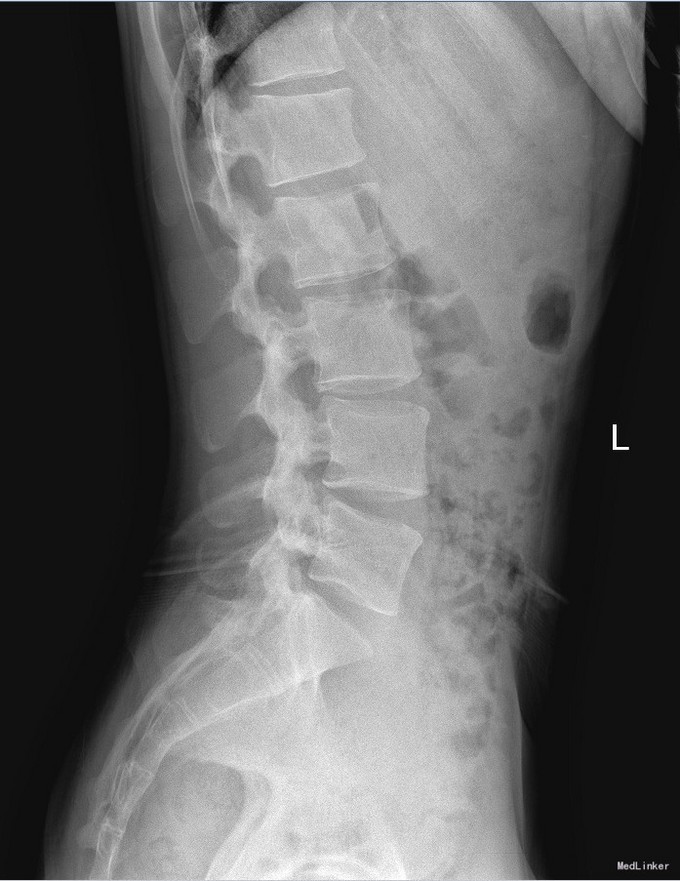

椎管侧隐窝占位1例

主诉 病史

左侧下肢放射痛1月加重2天

查体 辅查

腰椎前屈受限,腰4-5左侧棘突旁压痛,左侧直腿抬高试验小于30°,肌力正常。

诊断 处理

腰椎椎管内占位 腰椎后路开窗减压+椎间融合+内固定术